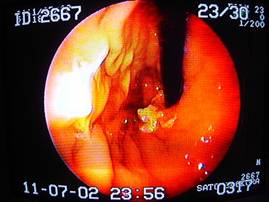

ん? なにやら怪しいものを発見。もう少し接近してみましょう。

画面左上に、もやもやした異物を確認。

これから摘出を試みます。